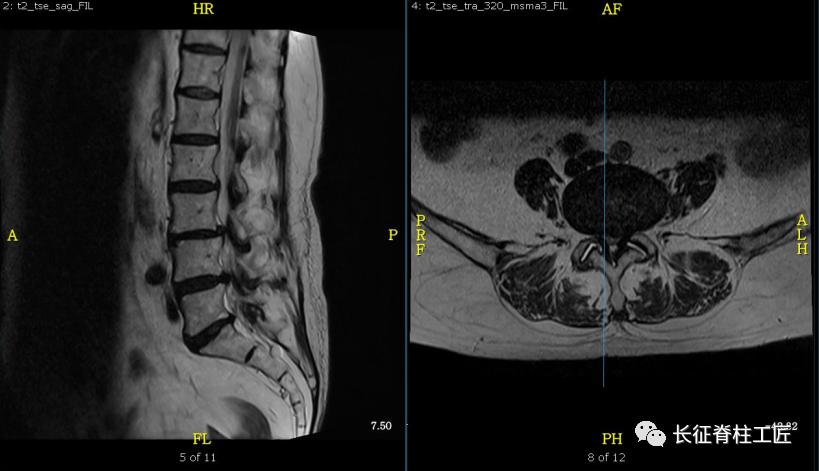

入院检查,腰部疼痛,后伸时加剧,局部压痛,双下肢肌力减退。X线检查,L4、L5骨质增生,MRI显示L4/L5、L5/S1椎间盘突出,马尾神经受压明显,被确诊为腰椎管狭窄症。

马尾神经是脊髓和周围神经的桥梁,脊髓的末端一般位于第2腰椎水平(腰椎共5节),脊髓末端就接着马尾神经,第2腰椎以下的腰椎管狭窄或腰椎间盘突出,压迫马尾神经,就会产生马尾神经综合征。

马尾神经综合征早期表现为会阴部麻木、感觉减退。当出现大小便功能障碍时,提示神经功能已经严重损害,应该立即采取急诊减压手术治疗,解除对马尾神经的压迫,尽可能挽救马尾神经功能。